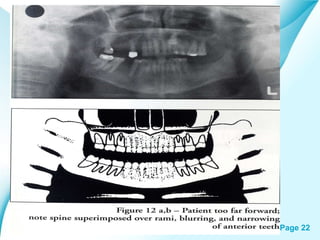

Page 21

Page 22

• 22.